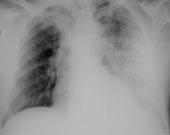

Pasient 2 . 69 år gammel kvinne med hypertensjon og hyperkolesterolemi, som de siste to år var blitt behandlet for obstruktiv lungesykdom. To dager etter hjemkomst fra ferie på Kreta fikk hun smerter basalt i brystregionen, sterke takvise smerter i høyre flanke ned mot lysken og temperatur på 39 ˚C. To dager før innleggelse tilkom kvalme og diaré. Hun ble henvist sykehuset etter en ukes sykdom under diagnosen pyelonefritt. Røntgen thorax ved innkomst viste høyresidig pneumonisk infiltrat, det ble også påvist pyuri. Man startet behandling med ampicillin intravenøst. Hun var ved innleggelse i god allmenntilstand, men i løpet av de første tre døgn utviklet hun oksygeneringsproblemer. Nytt røntgen thorax fire dager etter innkomst viste betydelig progrediering av fortetninger, med nye fortetninger også på venstre side. På grunn av mulighet for legionellapneumoni ble antibiotikabehandlingen endret til erytromycin og cefotaksim. Femte døgn etter innkomst fikk hun tiltakende respirasjonssvikt og måtte respiratorbehandles. Hun ble raskt hemodynamisk ustabil med behov for høye doser adrenergika og store mengder væske. Hun fikk anurisk nyresvikt og måtte dialyseres. Fire dager etter oppstart av erytromycinbehandling kom det svar om funn av legionellaantigen i urin. Hun fikk et svært legemiddeleksantem og erytromycin ble erstattet med doksycyklin og rifampicin. Etter to uker i respirator ble tilstanden akutt forverret med uttalt acidose og abdominal distensjon. På vital indikasjon ble det gjort eksplorativ laparotomi, der man fant en dårlig sirkulert og ekstremt dilatert colon. Det ble også påvist dårlig sirkulasjon i øvrige tarmavsnitt, og pasienten døde på operasjonsbordet.